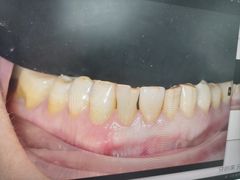

• 牙博士口腔品牌连锁(杨浦店)

• -牙博士口腔品牌连锁(杨浦店)

Angela | 25-03-28